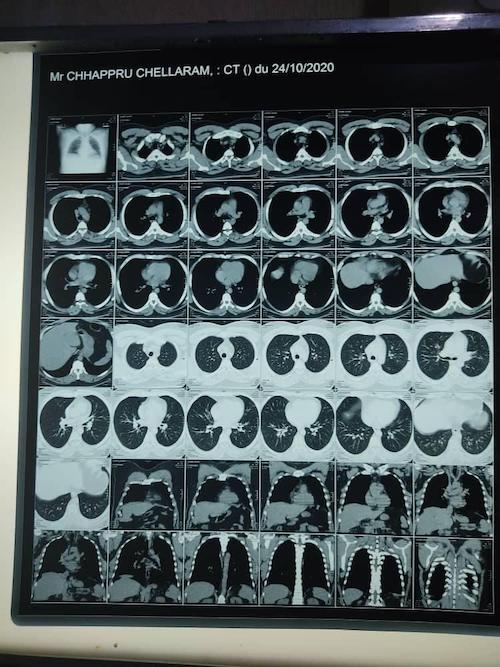

4ème preuve- Une photo des résultats de son scanner thoracique, montrant qu’il a une infection dans ses poumons.

10e preuve- Une photo de scans de ses poumons qui indique une infection causée par Covid-19.